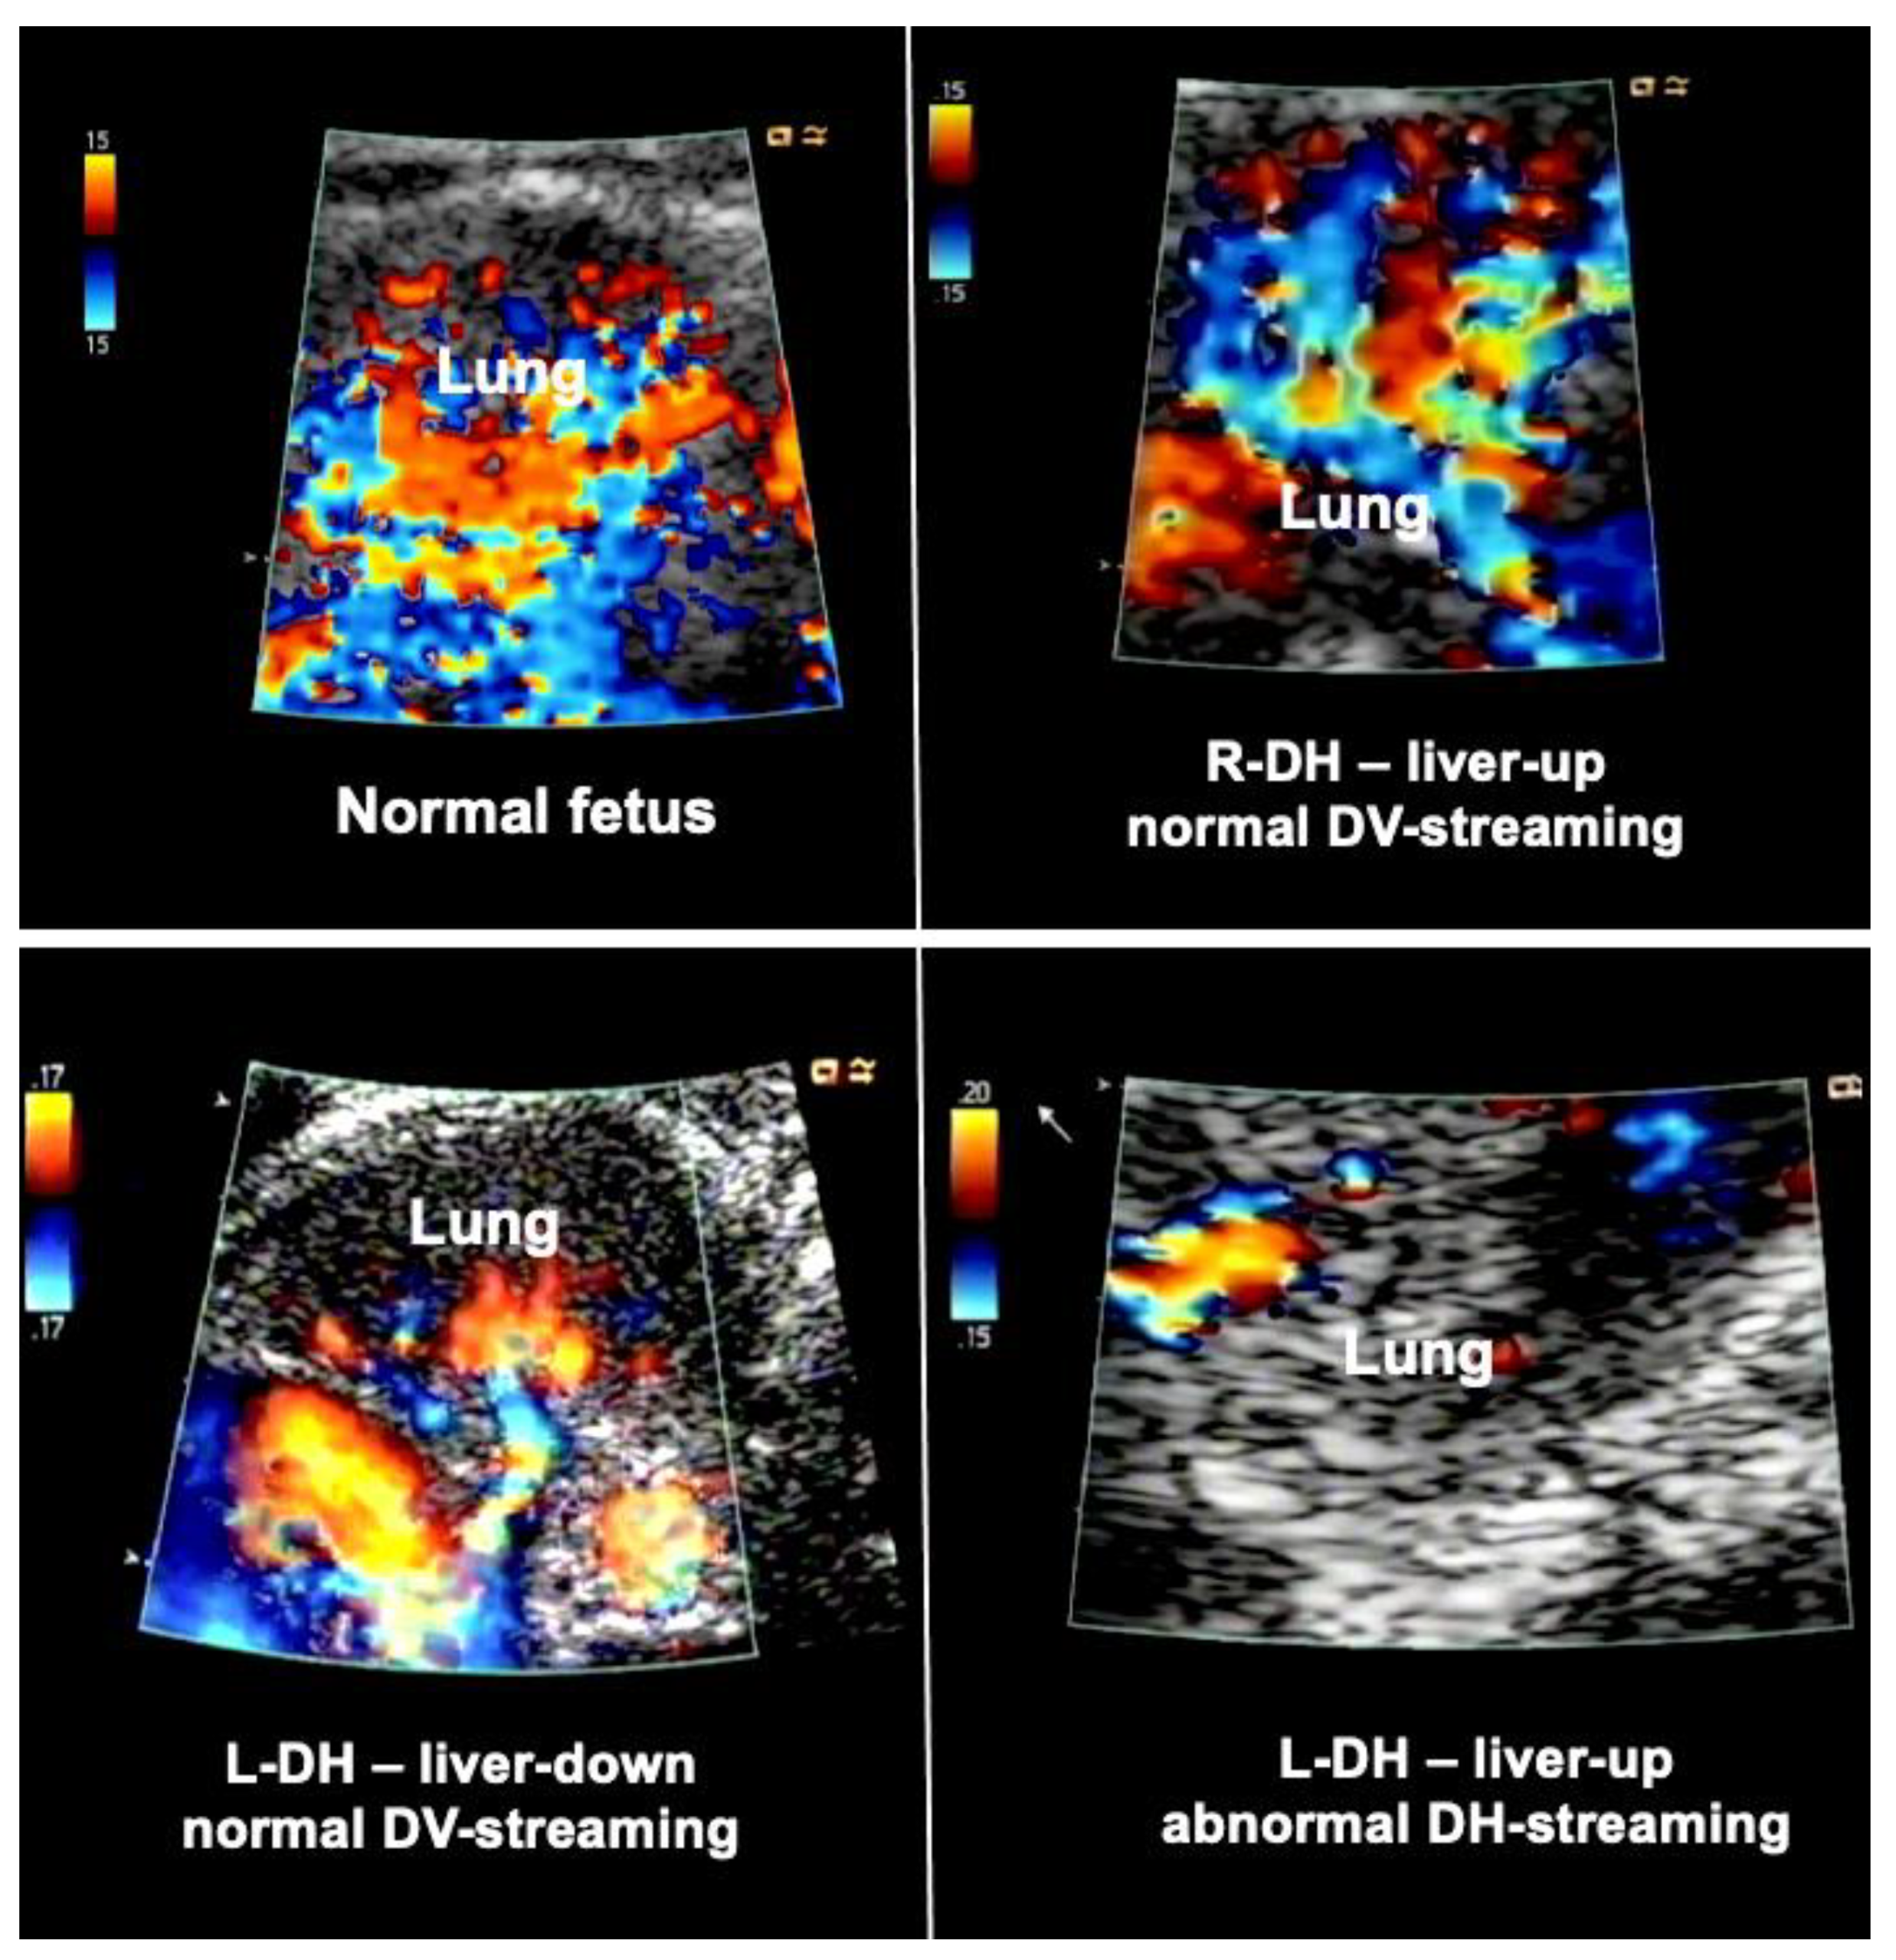

The principle is simple: A small fraction of supplemental oxygen being inhaled by pregnant women beyond 30 weeks of gestation crosses the placenta and increases the oxygen content of the fetal blood, thus inducing fetal pulmonary vasodilatation and a marked increase in lung blood flow (Figure 11). Through this mechanism, the preload from the increased pulmonary venous return challenges both hypoplastic left and right heart structures (Figure 11). Through providing 6 L/min of O2 via a face mask to the mother (approximately 35–40% oxygen) three times daily (8:00–12:00/14:00–18:00/20:00–23:00; total 10–11 h/day) from 32 + 0 to 34 + 0 weeks of gestation onwards until delivery, impressive degrees of catch-up growth can be observed in suitable cases [103].

Figure 11.

Acute loading effect of materno–fetal hyperoxygenation on the left ventricle in a fetus with hypoplastic left heart complex at 34 + 2 weeks of gestation. Top—color Doppler interrogation of a pulmonary vein before (left) and after 10 min (right) of materno–fetal hyperoxygenation demonstrates a marked increase in pulmonary flow. Bottom left—there is marked disproportion between the hypoplastic left (LV) and the dilated right ventricle (RV) before hyperoxygenation (BASELINE). Bottom right—after only 10 min of materno–fetal hyperoxygenation (OXYGEN), the left ventricle shows substantially improved filling at end diastole. Over several weeks, this effect results in catch-up growth of hypoplastic left heart structures. LA = left atrium; RA = right atrium.

Despite its enormous potential for fetuses with a wide spectrum of cardiovascular malformations, doubts were raised about the efficacy of the approach. It was feared that the increased pulmonary venous return would interfere with the normal right to left shunt across the oval foramen toward the left side of the heart, neutralizing additional loading of the left side of the heart. Whereas such a mechanism may be present in some fetuses, it is not at all applicable to fetuses with an imperforate atrial septum and an otherwise structurally normal heart. This subgroup presents with severe left heart underdevelopment (z-scores ≤ −3) and in my experience benefits particularly well from the volume challenge provided to the left side of the heart by chronic intermittent materno–fetal hyperoxygenation [104].

In other fetuses with fetal left heart hypoplasia, abnormal, preferential streaming of ductus venosus blood toward the right side of the heart can be observed [105]. This flow abnormality not only results in decreased flow across a patent oval foramen but is also associated with lower pulmonary blood flow. Both factors contribute to the development of left heart hypoplasia and may be ameliorated by materno-fetal hyperoxygenation.